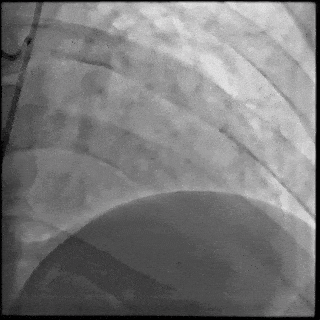

5月28日8:00,葛均波院士团队在中山医院16号楼16楼中伟厅成功连线喀什二院导管室,沪喀远程手术正式开始。8:35,新疆喀什二院导管室内股动脉入路通路建立后,行左右冠脉造影示左前降支中段存在85%的严重狭窄,狭窄位于血管分叉路口且紧邻心肌桥;且左回旋支中段近乎闭塞,血管细窄且迂曲,病变弥漫。8:59,葛院士于上海操控血管介入机器人主端,将指引导管送至左冠脉开口,并操控主支导丝和分支血管保护导丝通过狭窄病变,后送至前降支和对角支血管远端以建立轨道,同时利用介入机器人的微速调整功能避开心肌桥,以亚毫米级精准定位释放1枚支架。在成功处理患者左前降支病变后,葛院士通过搓捻机械操纵杆,远程精细调整导丝“进攻”方向,顺利通过左回旋支次全闭塞病变。因血管相对细小且病变弥漫,葛院士决定采用单纯球囊扩张术处理,即刻造影提示几乎无残余狭窄,避免了额外的支架植入。10:10,撤出所有导丝及导管,手术顺利结束。

【DSA图1.左冠治疗前造影】